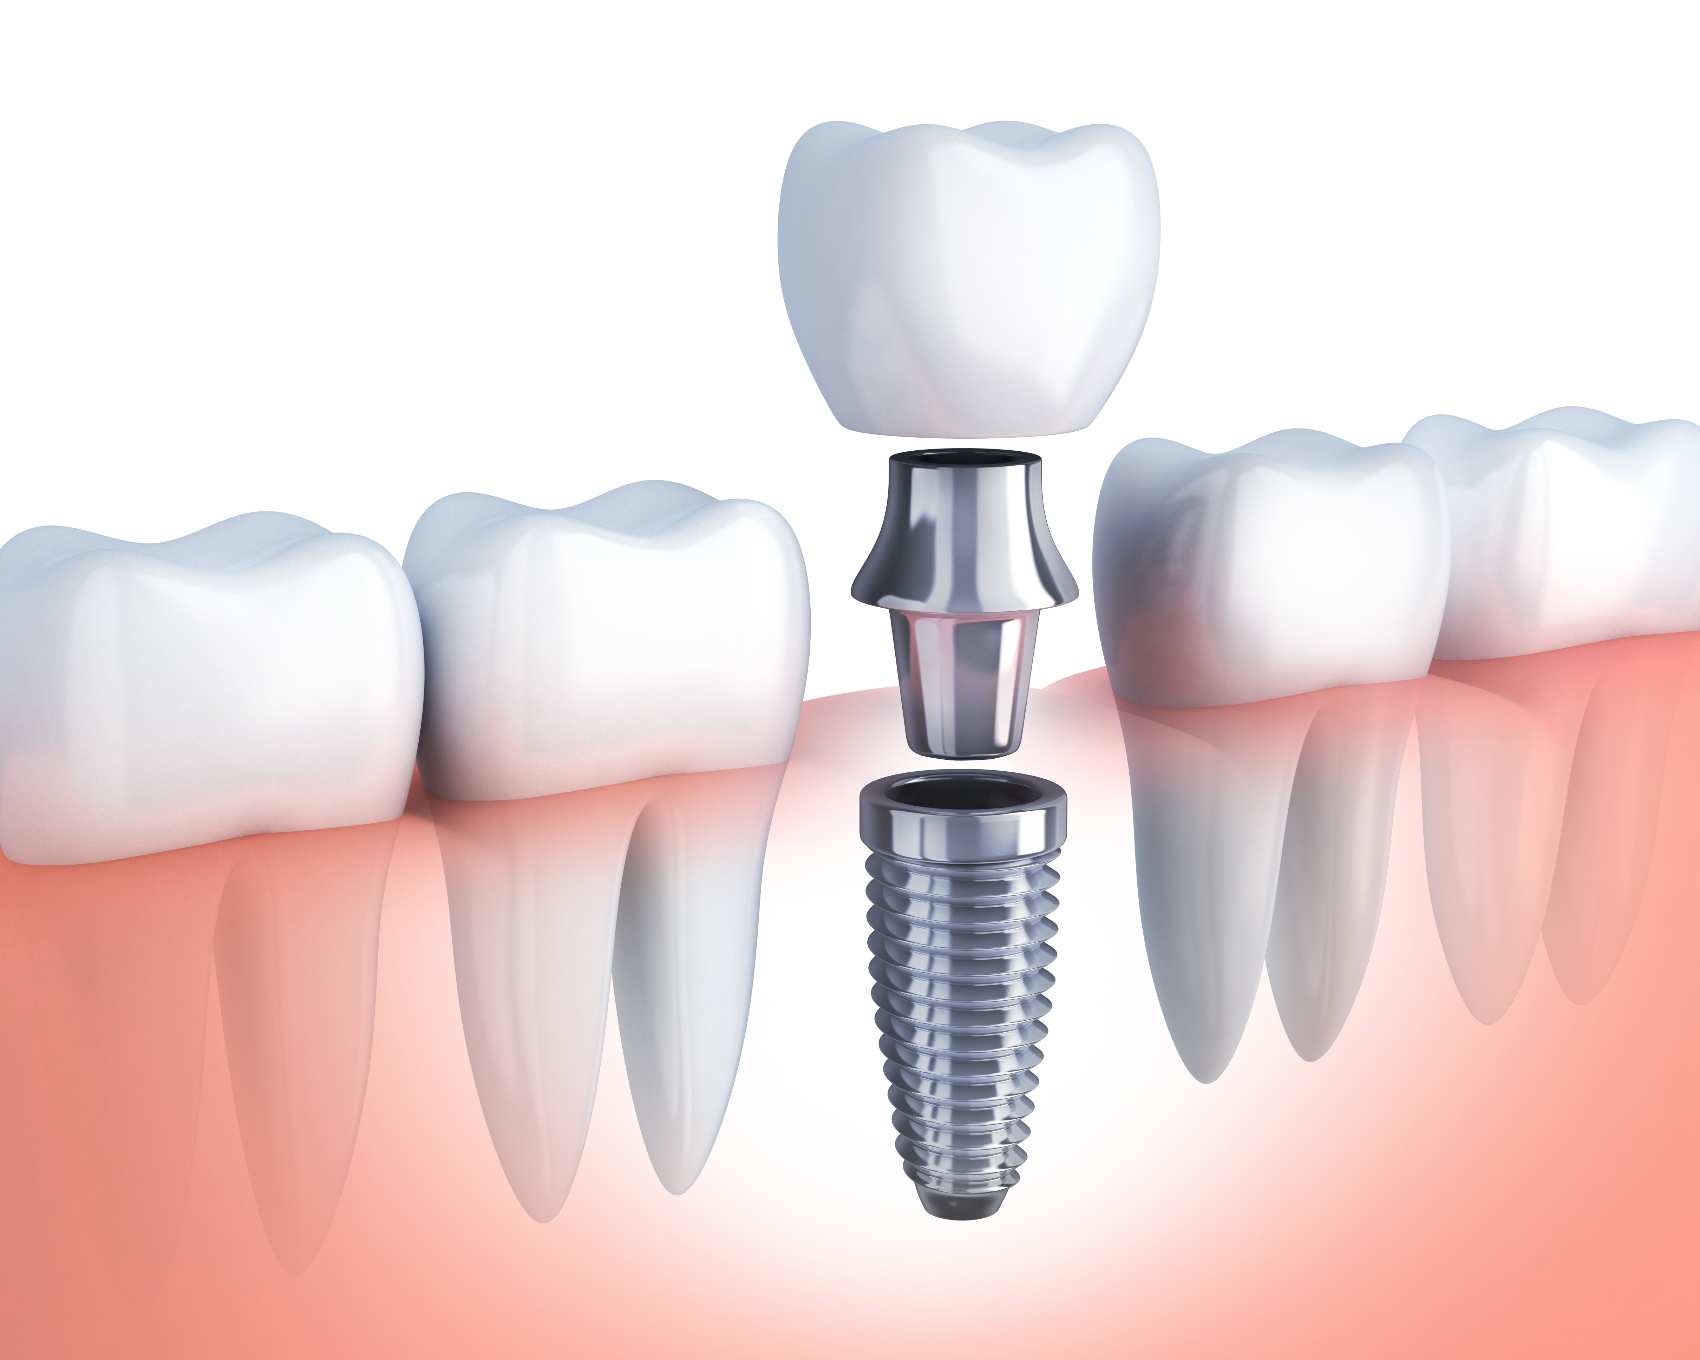

Implantologia

Colocação de implantes dentários no osso para suporte das novas coroas ou pontes.